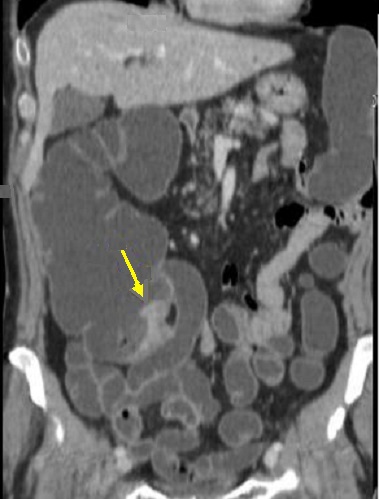

Aspect bourgeonnant

hyper-dense d'une adenocarcinoma du ceacum ( fleche

jaune ) . Image radiologique TDM en coupe coronale (

frontale ) . |

|

Même cas en coupe sagitale .

Aspect de masse du tumeur est bourgeonnant

hyper-dense intraluminale a bord irregulier (

fleche jaune ) |